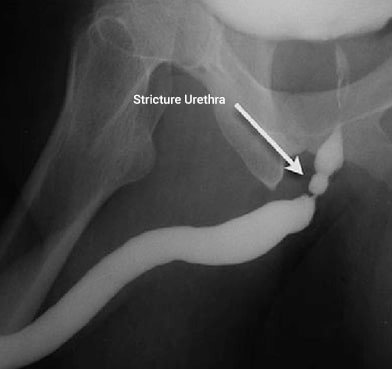

Üretra, mesanede biriken idrarın dışarı atılmasını sağlayan kanaldır. Bu kanalın herhangi bir bölümünde daralma oluştuğunda idrar akışı zorlaşır. Daralma ilerlediğinde mesane tam boşalamaz ve zamanla idrar yolu sisteminde basınç artışı meydana gelebilir.

Bu durum başlangıçta yalnızca işeme zorluğu gibi belirtilerle kendini gösterirken, ilerleyen dönemlerde daha ciddi sorunlara zemin hazırlayabilir.